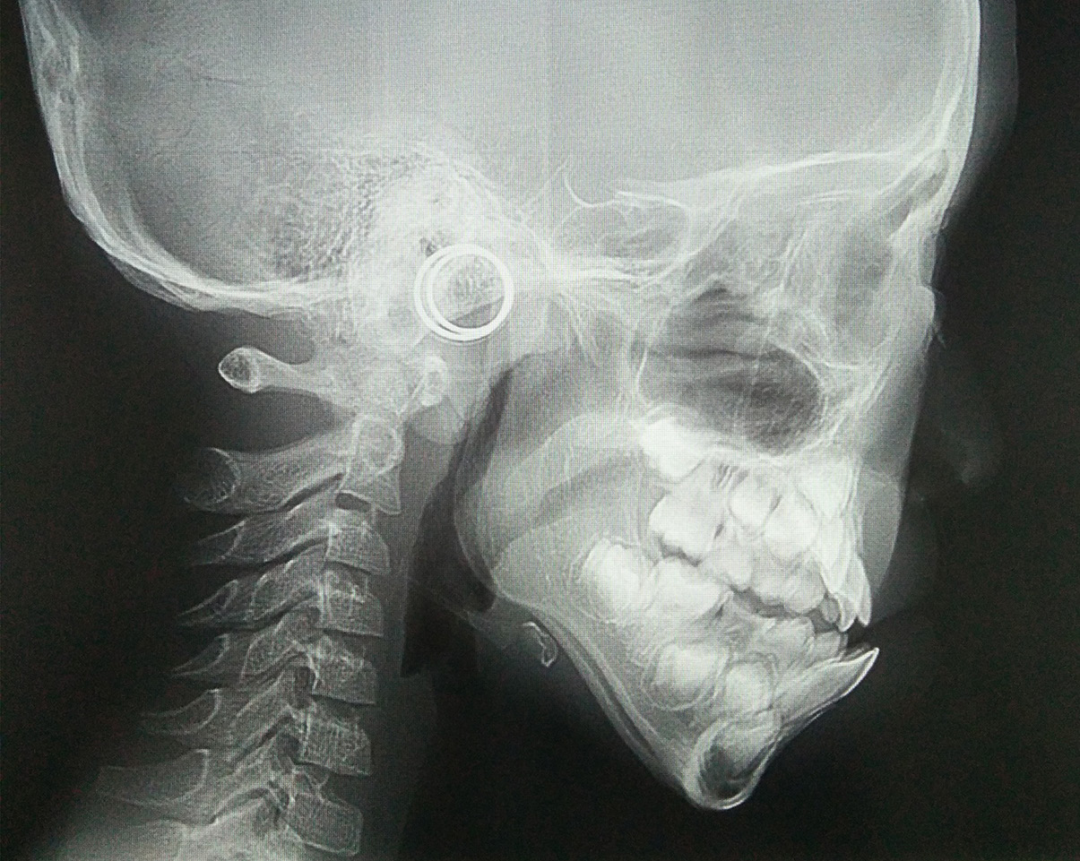

比如说这个孩子初诊时为替牙期,前牙对刃,但是患者家长拒绝接受矫正干预,一年半后复诊,前牙反颌重,并出现下颌前突。

头影测量中有一个方法简单有效——从 N 点(鼻根点)做眶耳平面的垂线,即 Mcnamara 线,上颌骨 A 点(上齿槽座点)距离该垂线的正常距离,0mm(儿童),1~2mm(成人);下颌骨 Pog 点(颏前点)距离该垂线的正常距离,- 6mm(儿童),- 2mm(成人)。

上颌后缩情况

下颌前突情况